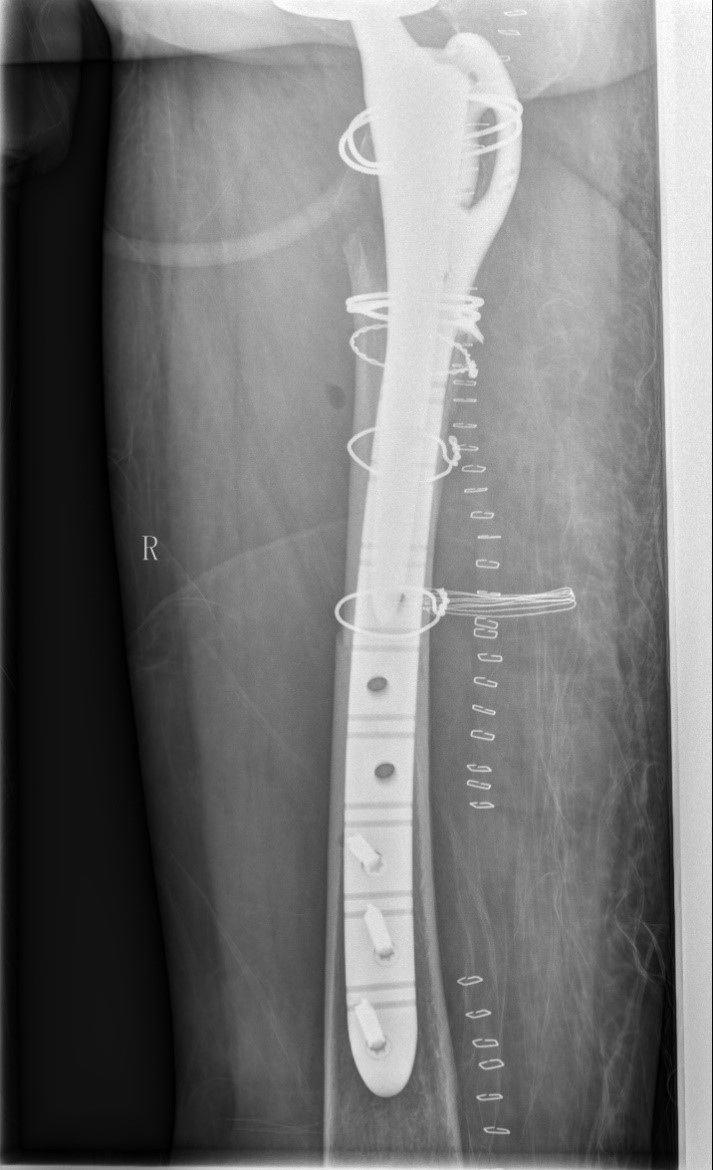

案例三:59岁女性假体周围骨折

患者情况:吴女士,5年前曾在我院接受人工髋关节置换术,近日因在家中地板湿滑处摔倒,导致假体周围骨折。

治疗难点:

1.摔伤后需评估假体是否松动;

2.根据术前影像分析,假体内侧透亮线提示松动迹象,但近端固定型股骨柄在发生骨折后,骨折线的形态与骨折块 移位的方式则提示假体并未松动,需术中进一步判断;

3.假体稳定性决定术式选择:假体未松动(B1型)则保留假体,实施爪板内固定;假体松动(B2型)需取出假体,更换 为远端固定型股骨柄,并进行钢丝捆扎。

4.针对手术方案的复杂性与不确定性,需要与患者及家属充分沟通,明确术中可能面临的风险,并取得他们的理解与 信任,才能为手术顺利实施奠定基础。

5. 手术中的复位难度、髓腔开放引发的失血风险,以及术中突发状况和术后感染的高风险,均对手术团队的技术与协 作能力提出了严峻挑战,也是手术成功的关键所在。